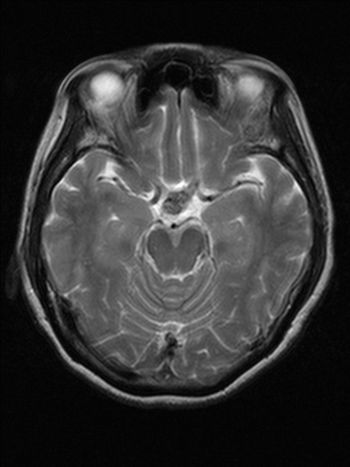

A 55-year-old female presented with a one-month history of excessive thirst and polyuria. She had an operation for adenocarcinoma of the lung about 21 months ago.